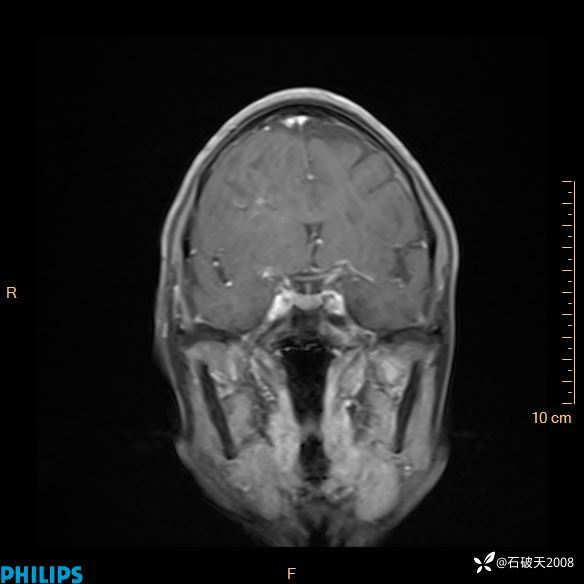

2024.2.21MR

增强轴位